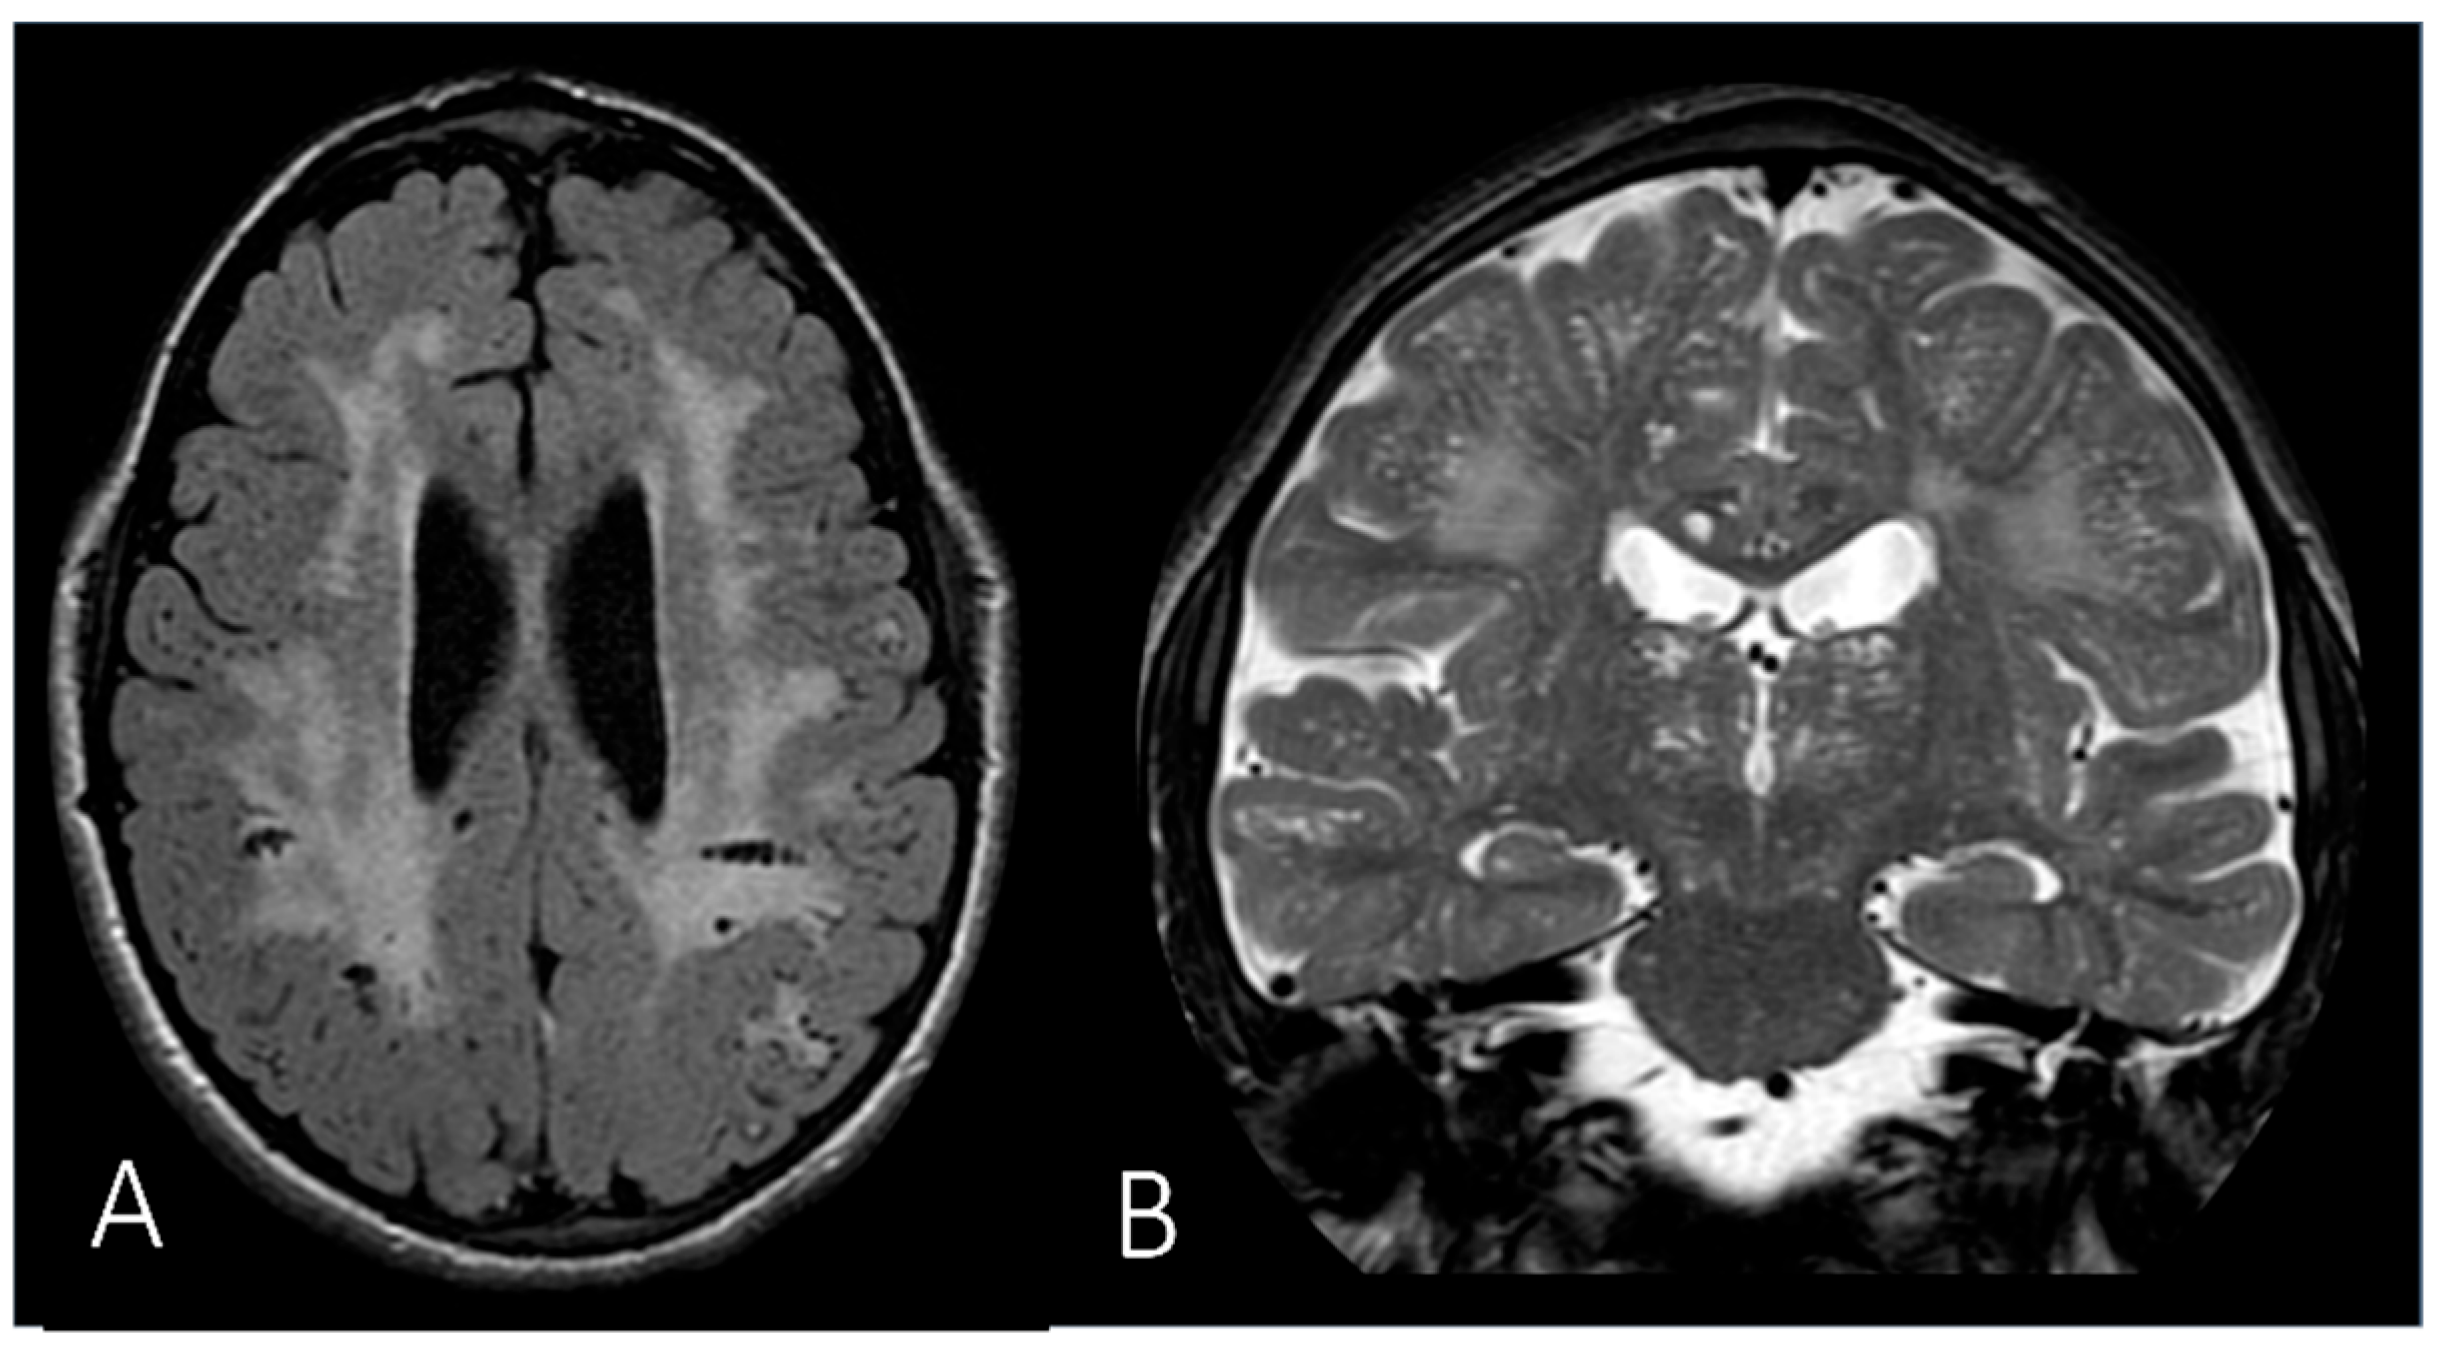

| White matter abnormality | + (mild) | + | + | N.A. | + | |||

| Brain atrophy | + | + | N.A. | |||||

| Hydrocephalus | + (mild) | + | N.A. | |||||

| Enlarged perivascular spaces | + | + | + | N.A. | ||||